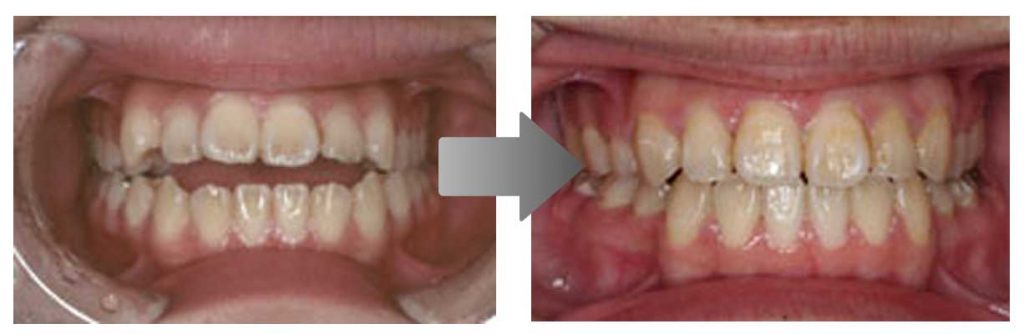

矯正の症例

1) 矯正前の状態

叢生(そうせい…歯がデコボコしたり、重なりあって生えていたりする状態)

開咬(かいこう…奥歯はしっかり噛んでいるが、上下の前歯が噛まずに隙間がある状態)